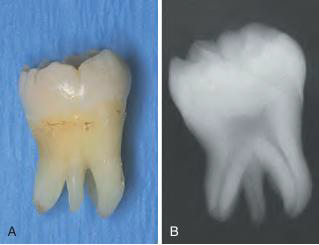

Dentigerous cyst (DC) | follicle 分離 | 38,48 | 10 - 30y |

![]() |

|